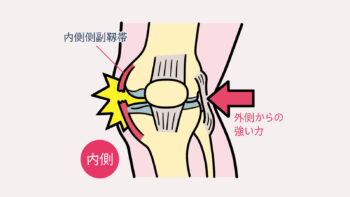

🦵 内側側副靭帯(MCL)損傷とは

内側側副靭帯(MCL)損傷とは、膝関節の内側にある

「内側側副靭帯(Medial Collateral Ligament)」が伸びたり、部分的に断裂

あるいは完全に断裂してしまう外傷です。

MCLは、膝が内側に開く動き(外反ストレス)を防ぎ、関節の安定性を保つ重要な

役割を担っています。特に歩行や走行、方向転換などの日常動作やスポーツ動作において、

膝を安定させるために欠かせない靭帯です。

■ 主な原因

MCL損傷は、膝の外側から強い力が加わることで起こります。